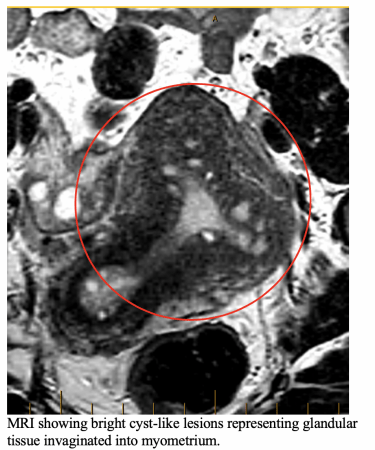

MRI detect bright signal glands (adeno) within muscle wall ( myosis), as well the reactive muscle cell changes ( seen as thickening of junctional zone).